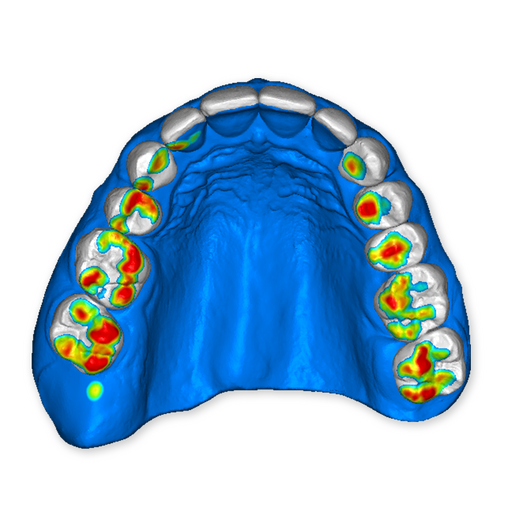

The DSD Interdisciplinary is a digital wax up of the upper and lower arches, designed considering a facially-driven, clinical and functional analysis of the patient.

It is our most comprehensive planning option, and includes all the 3D treatment simulations needed for each case, such as ortho, perio, implants, grafts and orthognathic surgery.

Our 3D simulations showcase various treatment suggestions, facilitating a deeper understanding of the required procedures. This leads to the creation of a broader treatment plan and enables a more efficient communication with your patients.